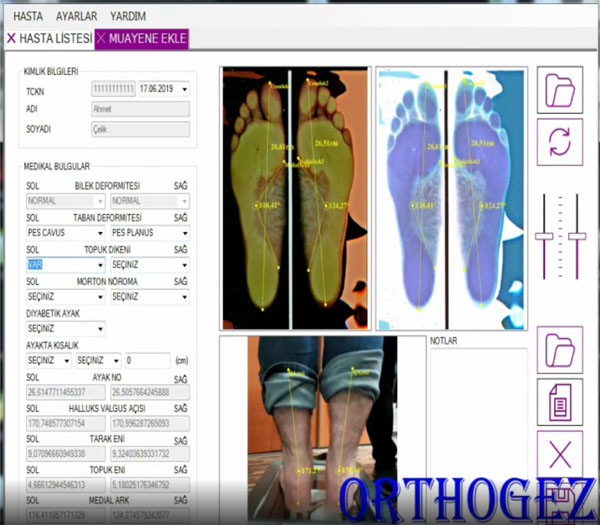

1. Dijital Ayak Analizi

MYS Analiz Sistemi ile ayağınızın statik ve dinamik ölçümleri alınır. Basınç noktaları, yük dağılımı, kavis yapısı ve yürüyüş biçimi detaylı olarak analiz edilir.

- Statik faz analizi (ayakta durma)

- Dinamik faz analizi (yürüme)

- Basınç haritası çıkarma

- Detaylı Türkçe raporlama